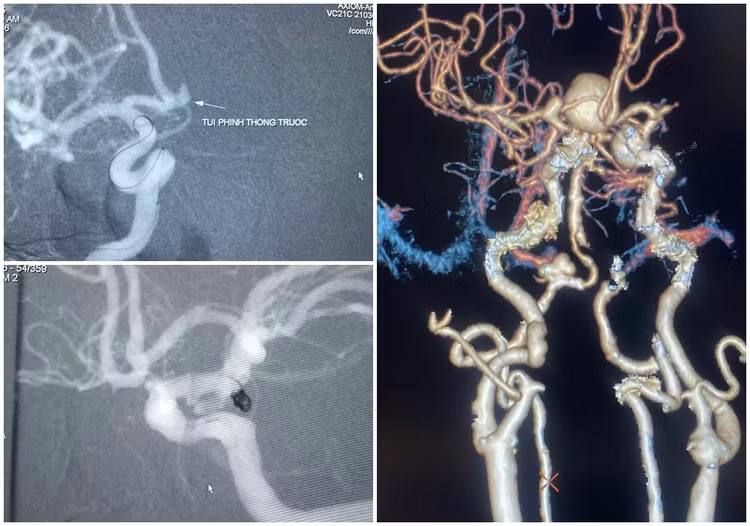

Tiếp nhận bệnh nhân trong tình trạng nguy kịch, bác sĩ chỉ định chụp mạch não, kết quả cho thấy bệnh nhân bị xuất huyết dưới nhện do vỡ phình động mạch cảnh trong phải. Nếu không kiểm soát tốt, máu có thể tiếp tục tràn vào khoang dưới nhện, gây suy giảm ý thức, hôn mê sâu.

Nhận định là ca cấp cứu tối khẩn, hội chẩn đa chuyên khoa Hồi sức tích cực, phẫu thuật thần kinh, chẩn đoán hình ảnh quyết định can thiệp nút mạch cầm máu khối phình bị vỡ nhằm ổn định tình trạng xuất huyết và tránh nguy cơ tái xuất huyết cho người bệnh. Sau vài ngày điều trị, bệnh nhân tỉnh táo, hồi phục sức khỏe tốt, đi lại được sau can thiệp, không bị di chứng thần kinh.